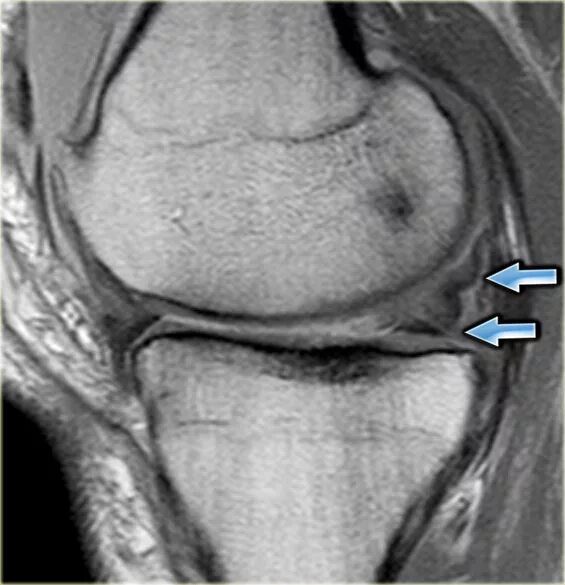

Stoller 2 разрыв мениска